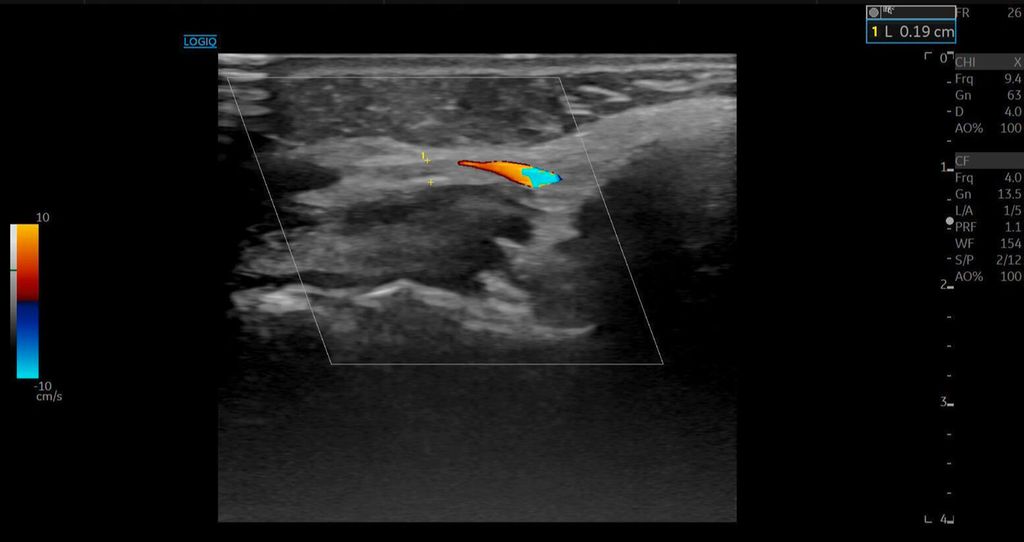

Die Duplexsonografie ergab folgende Befunde (Abb. 5 und Abb. 6):

Der Durchmesser der A. angularis und A. facialis hatte sich nahezu verdoppelt.

Die systolische Spitzengeschwindigkeit (PSV) stieg von 20cm/s auf über 100cm/s.

Die enddiastolische Geschwindigkeit (EDV) betrug nun 20cm/s, was auf eine periphere Vasodilatation und eine Wiederherstellung der Makrozirkulation hindeutete (Abb. 7).